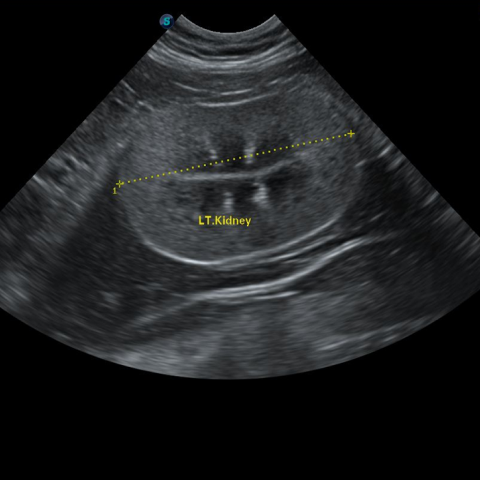

½ÅÀåÇ÷¾×°Ë»ç(BUN, CREA, P, ÀüÇØÁú), SDMA(½ÅÀå ¿©°úÀ² °Ë»ç), Ç÷¾Ð, ¿ä °Ë»ç, º¹ºÎ ÃÊÀ½ÆÄ °Ë»ç¸¦ ÅëÇØ ½ÅÀ庴 ´Ü°è¸¦ Áø´ÜÇÕ´Ï´Ù.

µ¶¼º¹°ÁúÀ» ¸Ô¾úÀ» ¶§, ±¸Å䳪 ¼³»ç°¡ Áö¼ÓµÉ ¶§, ´ÙÀ½ ´Ù´¢ °¡ ÀÇ½ÉµÉ ¶§, °Ç°°ËÁø ÇÒ ¶§, ¸¶Ãë Àü °Ë»ç ½Ã Á¤¹Ð°Ë»ç·Î ½ÅÀå°Ë»ç¸¦ ÁøÇàÇÕ´Ï´Ù.